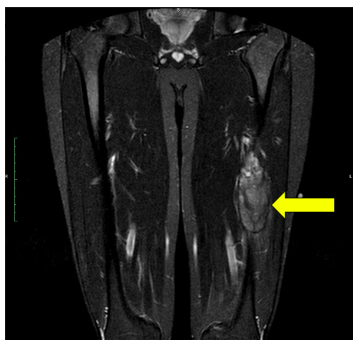

Ewing's Sarcoma is an aggressive, cancerous (malignant) tumor that, if left unchecked, will grow and destroy the normal bone. Clinically, they manifest as localized pain (usually worse at night), fever, and swelling. The affected area may be tender and warm. Patients may also notice night sweats and weight loss. Early and effective treatment is essential, as Ewing's Sarcoma also has the ability to spread to other parts of the body, known as metastasis. Advanced imaging, such as whole body bone scans and CT of the chest/abdomen/pelvis, are used to check if the cancer has spread, or metastasized, throughout the body.

An example of an MRI depicting Ewing's sarcoma in the lower extremity is shown.

Ewing's MR